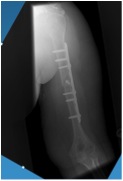

- Fixing the fragments in the right place with a plate and screws. An incision is made down the back of the elbow. The pieces of bone are put back into their correct place and held by a plate and screws. Because the pieces are held together in this way early movement of the joint is possible and stiffness is limited.